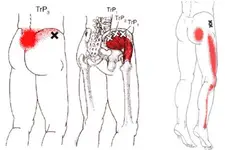

Bu durumlar, belde ağrı, bacaklarda uyuşma, karıncalanma ve güçsüzlük gibi çeşitli semptomlara yol açabilir. MR Görüntüleme Yöntemi Manyetik Rezonans Görüntüleme (MR), vücut içindeki dokuların ayrıntılı görüntülerini elde etmek için manyetik alanlar ve radyo dalgaları kullanan non-invaziv bir görüntüleme tekniğidir. MR, yumuşak dokuların görüntülenmesinde X-ışınlarına göre daha üstün sonuçlar verir. Bel fıtığı gibi durumların tanısında oldukça etkili bir yöntemdir. Bel Fıtığı MR Özellikleri Bel fıtığı MR görüntülerinde dikkate alınması gereken bazı önemli özellikler şunlardır:

Bel fıtığı tespit edilse bile fizik muayene sonuçlarıyla çelişiyorsa, bu durum hastanın tedavi sürecini olumsuz etkileyebilir. Yanlış bir tıbbi değerlendirme, hastanın yanlış bir tedavi almasına neden olabilir. Bu nedenle, klinik bulgular ile görüntüleme sonuçlarının birlikte değerlendirilmesi son derece önemlidir. Tedavi planı, her iki verinin bir arada göz önünde bulundurulmasıyla daha sağlıklı bir şekilde oluşturulmalıdır.